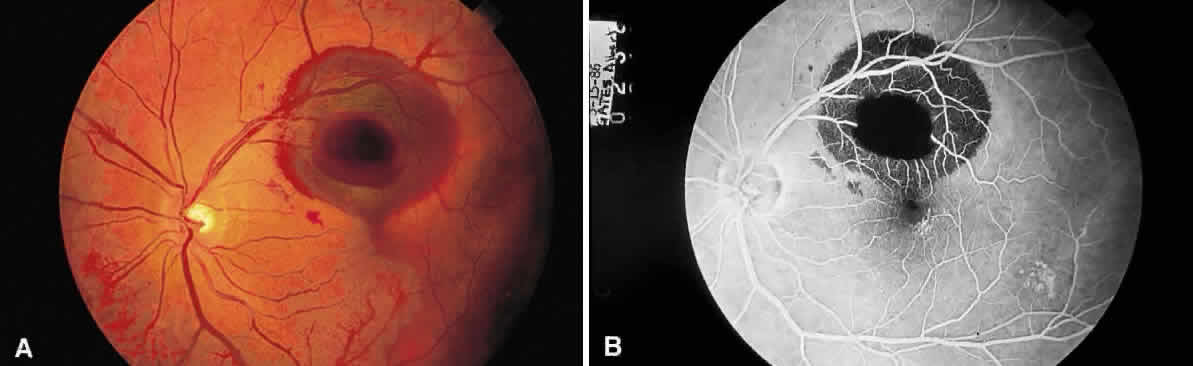

In contrast to lattice degeneration, which affects the inner retinal layers, paving stone degeneration (cobblestone degeneration, peripheral chorioretinal degeneration) affects the outer retinal layers.24 Ophthalmoscopically, paving stone lesions appear as well-demarcated concave zones of depigmentation (Fig. 62A and B). Frequently, the depigmentation is so marked that the larger, outermost choroidal vessels may be seen running through the lesion. The lesions usually are located just posterior to the ora serrata. These depigmented zones may appear individually or may coalesce into larger lesions that demonstrate a scalloped border with pigmented edges.

Fig. 62. A. Paving stones just anterior to the ora serrata. (William Benson: Wills Eye Atlas of Ophthalmology, Fig. 4-58. Philadelphia, Lippincott-Raven, 1996) B. Photograph of the calottes of an autopsy eye showing paving stone degeneration. C. Photomicrograph of paving stone degeneration. The vitreous (v) and choroid (c) are marked for orientation. The retina is detached by an artifact, except in the zone of the paving stone lesion. Notice that the photoreceptors are present to either side of the lesion but not within the lesion. The pigment epithelium also is absent in the area of the lesion. The ophthalmoscopist therefore looks through transparent retina onto choroid and sclera, which accounts for the color of the paving stone lesion.

Histologically, there is loss of the outer retinal layers, including the retinal pigment epithelium (see Fig. 62C). The loss of pigment epithelium accounts for the color of the lesion and permits the larger choroidal vessels to be viewed ophthalmoscopically. The thinned neurosensory retina is firmly adherent to underlying Bruch's membrane and to the reactive pigment epithelium at the margins of the lesion. The pigment epithelial changes account for the clinically observed black border of these zones. Unlike retinal lattice degeneration, there is no change in the overlying vitreous and no pathogenic relation to retinal detachment. In fact, the histopathologic appearance of paving stone degeneration resembles the chorio-retinal adhesion seen after therapeutic cryopexy. The forward advance of a retinal detachment does not extend beyond the posterior edge of a paving stone lesion.